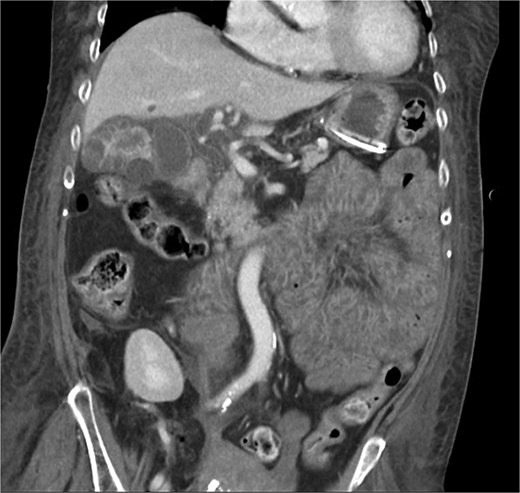

A 63-year-old female with a history of developmental delay, hypertension, hyperlipidemia, paroxysmal atrial fibrillation, hyperparathyroidism status post-parathyroidectomy, and ESRD on intermittent hemodialysis who presented for a scheduled left kidney transplant. Her post-operative course was complicated by subcapsular hematoma resulting in significant blood loss and requiring resuscitation in the trauma-surgical intensive care unit (TSICU); acute hypoxic respiratory distress on post-operative day (POD) 2, necessitating reintubation and escalating vasopressor support; and bacteremia and xanthogranulomatous cholecystitis identified on POD 3, confirmed by imaging (Figs 1 and 2) and blood cultures positive for Klebsiella pneumoniae and Enterobacter cloacae with Cefotaxime-Munich (CTX-M) resistance.

CT chest abdomen pelvis with IV contrast coronal view. The common bile duct is visible and without dilation, note multiple intramural hyperattenuating nodules and gallbladder wall hyperenhancement. This image also shows diffusely edematous jejunum indicative of systemic hypoperfusion.

XGC is typically diagnosed through imaging and histopathological examination. In this case, computed tomography (CT) revealed findings consistent with XGC, including gallbladder thickening and inflammatory changes [3]. However, definitive diagnosis was confirmed by blood cultures and the clinical course. The overlapping features with cholecystitis and biliary tract malignancies pose diagnostic challenges, particularly in acutely ill patients. In transplant recipients, where symptoms may be atypical and infection progresses rapidly, clinical suspicion and early intervention are paramount.